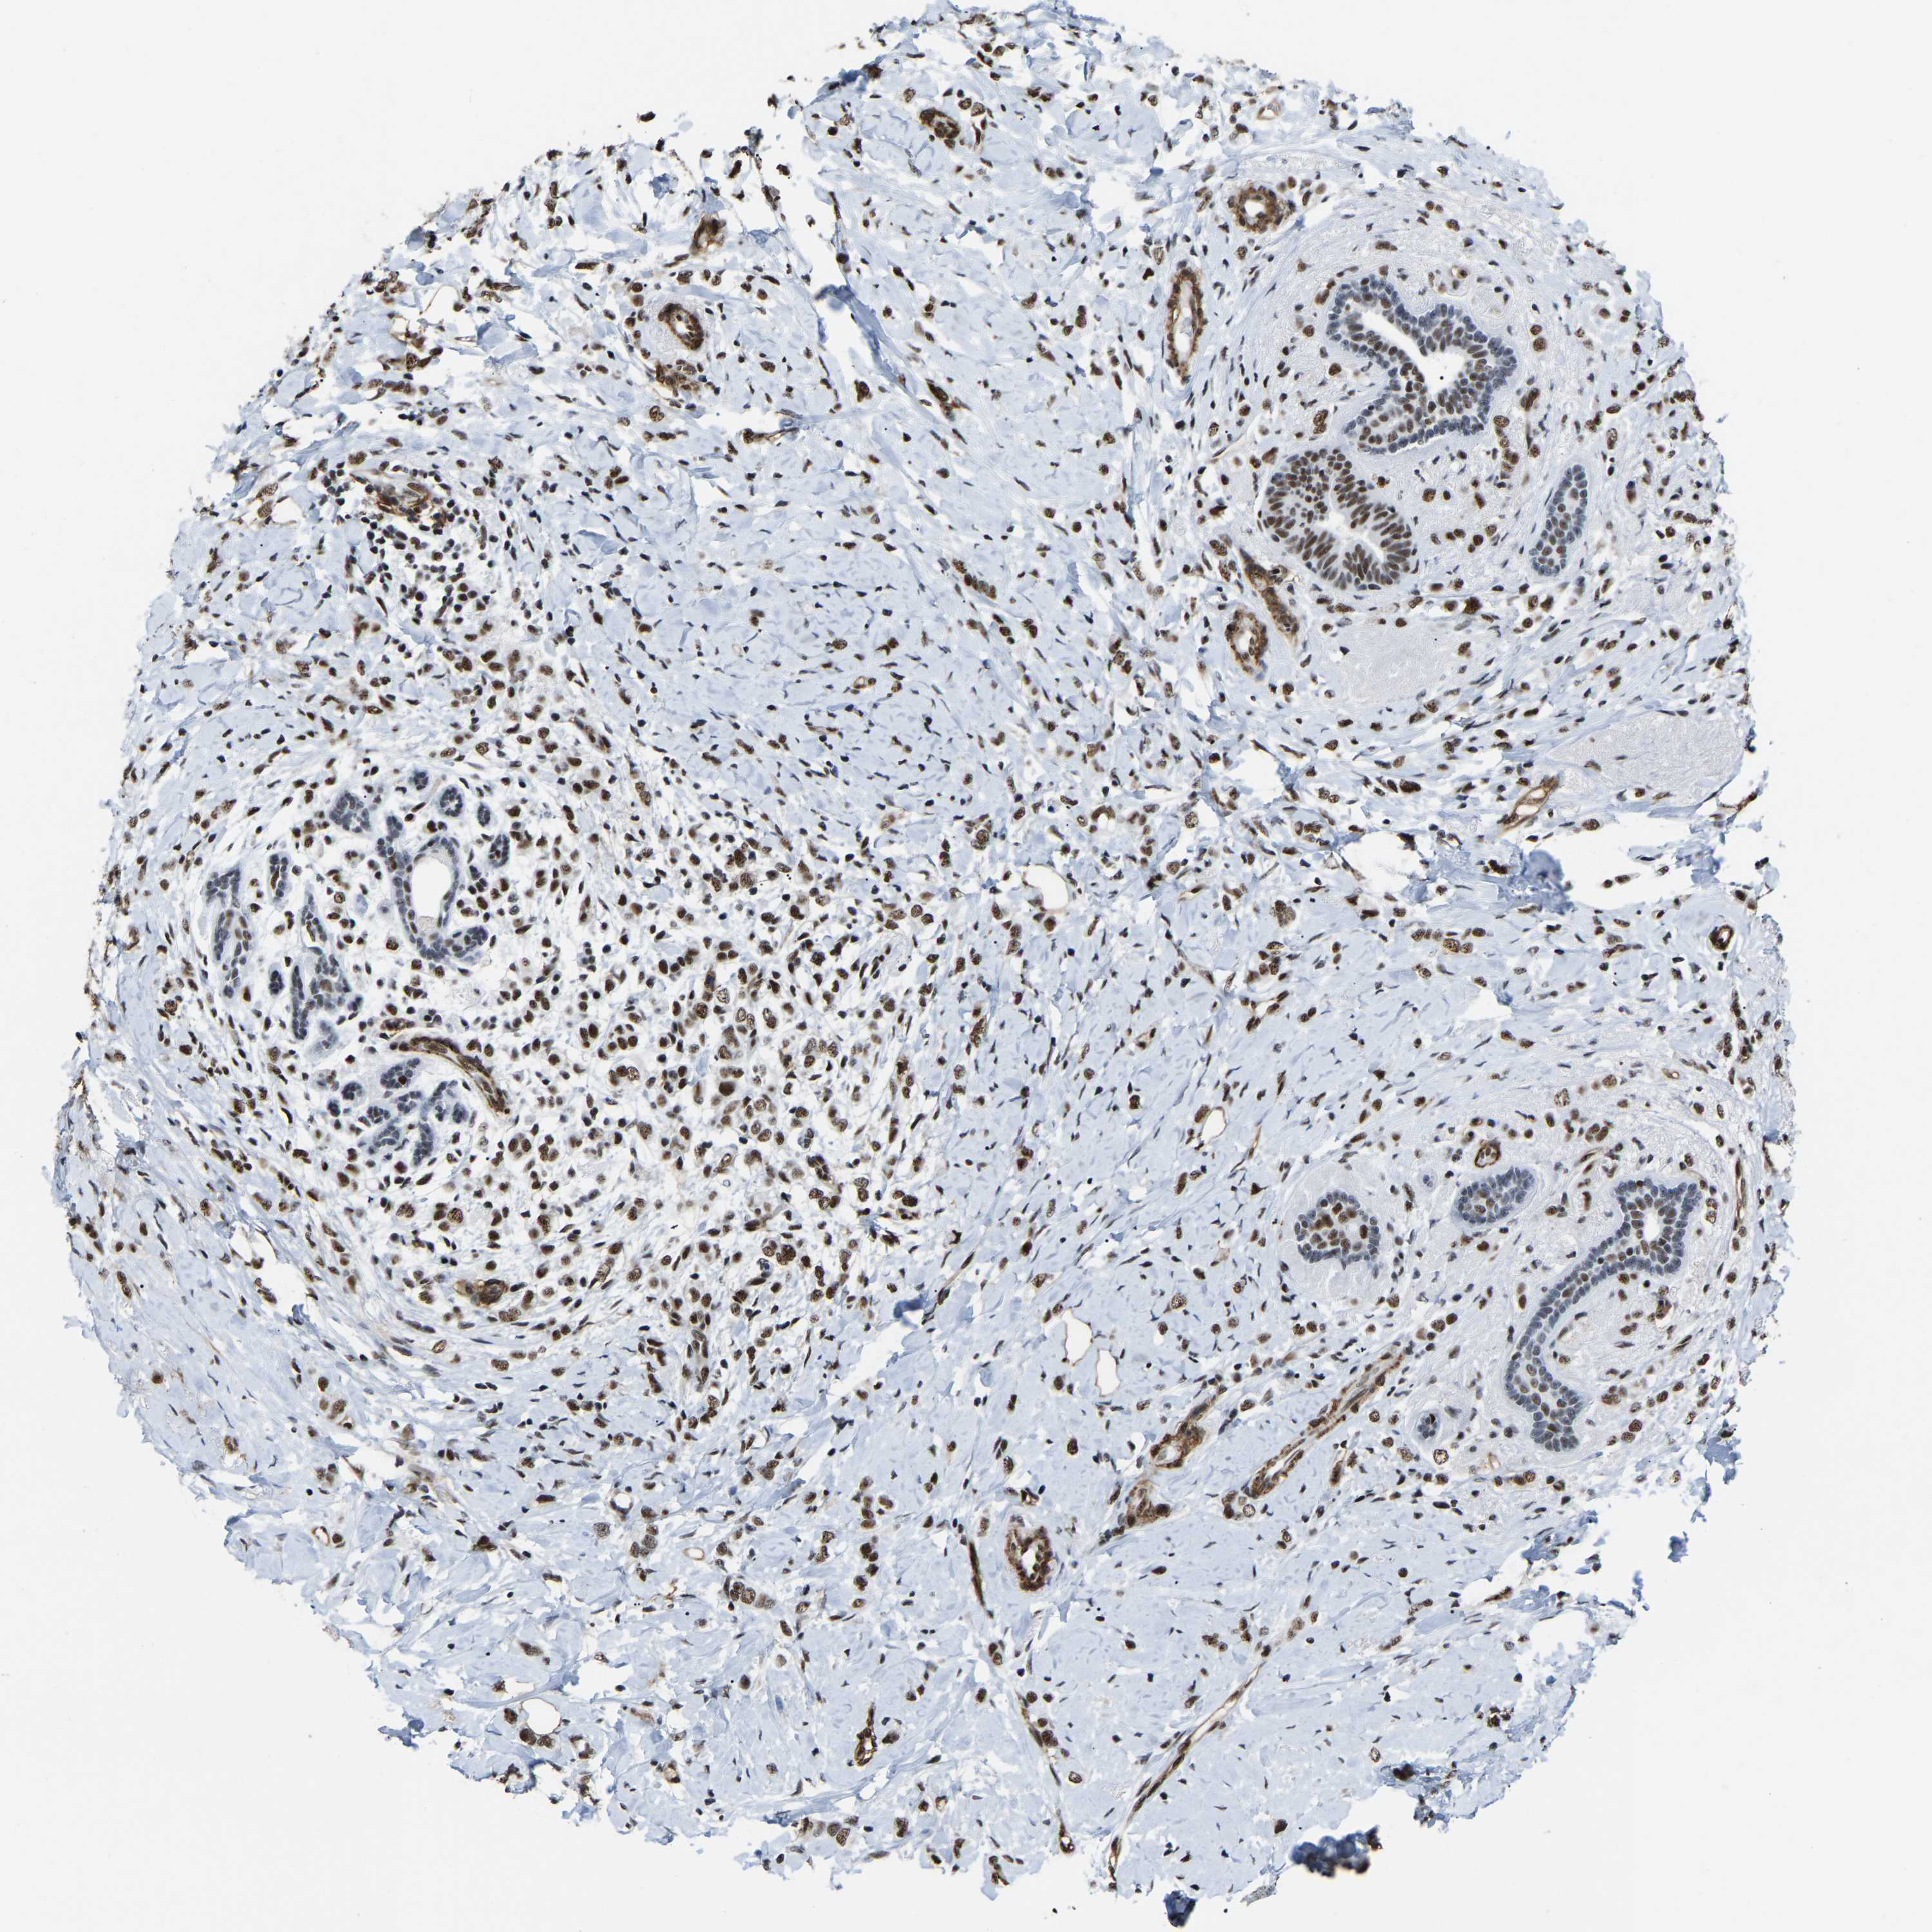

BRCA TCGA BRCA VALIDATION PROTEIN EXPRESSION